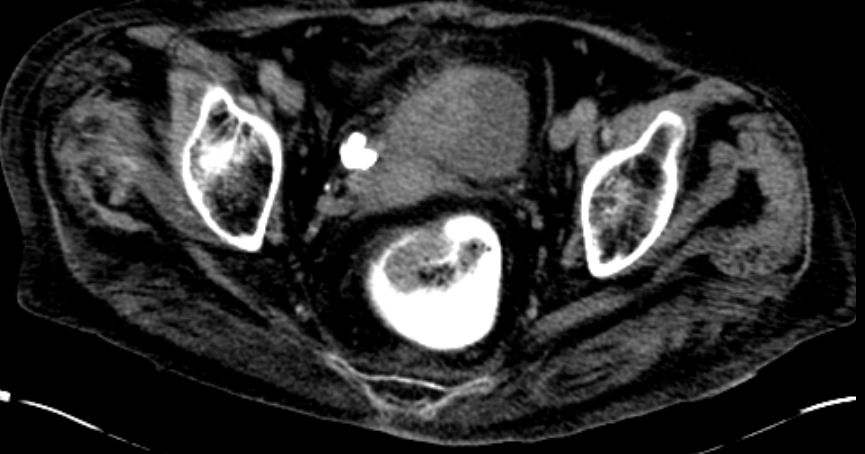

| Rektus - Infiltration | 80-jähriger Mann mit Haematurie seit 6 Monaten.

Endoskopisch ein ausgedehnter Blasentumor gesehen, der von der rechten

Seitenwand zum Dach und der Hinterwand zeiht. Der Tumor war zum Teil solide

infiltrierend wachsend, zum Teil papillär und zerfallen. Eine vollständige

Abtragung war nicht möglich. Das CT zeigte, dass dieser Tumor auch das

anliegende Fettgewebe und den Musculus rectus rechts infiltriert.![]() | |||

Rechts lateral anliegend stellte sich eine 11 mm große

Lymphknotenmetastase dar.![]() |